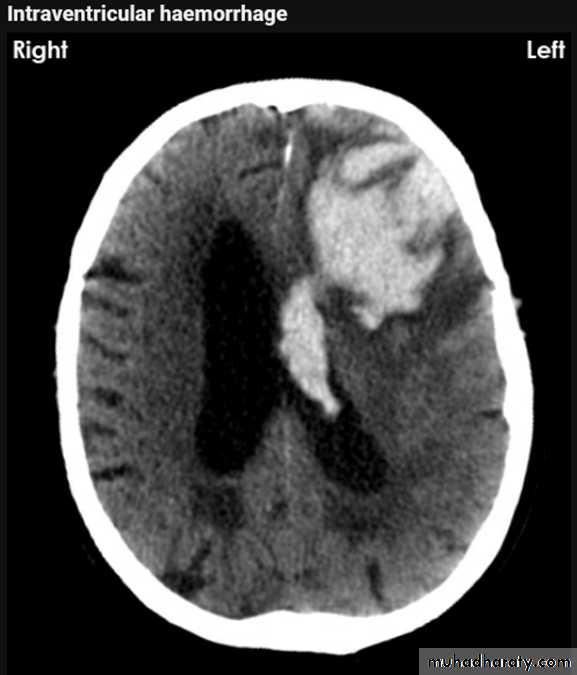

Intra ventricular IVH

Acute Intra cerebral hematoma

CT finding :Hyper dense area , surrounded by edema , any where within the brain parenchyma.

Shifting of the midline

Compression of the ipsi lateral ventricle .